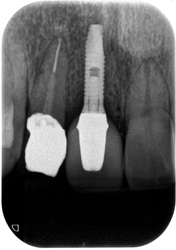

治療前

治療後

治療前

治療後

左下前・小臼歯部のブリッジによる荷重負担の為、隣在歯を守るインプラントを選択。

左下4番に単独インプラントを埋入。

オペ後、骨との密着値も良く、約2ヶ月後には、ジルコニアを装着し終了。

リスクとしては外科的侵襲がある。デメリットは、保険外診療の為、経済的負担がある。

費用 53万(税込)(オペ・仮歯・最終補綴物まで含む)